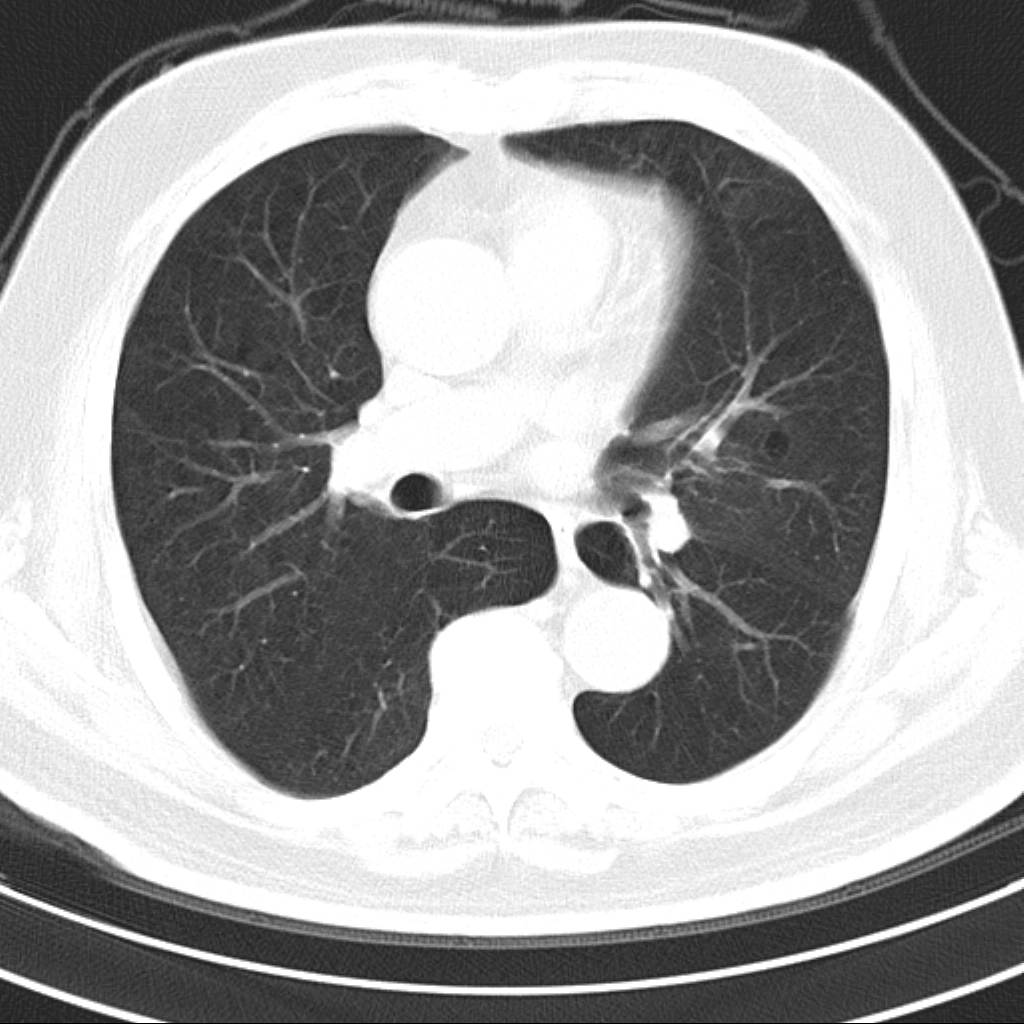

标题: CT18644:男,82岁,体检发现左肺阴影. [打印本页]

标题: CT18644:男,82岁,体检发现左肺阴影.

岁数太大,没有增强。麻烦见过的,给个诊断,顺便再说说病因

左侧中心型肺癌并粘液栓形成。很典型的。手套征。

支持 左肺上叶中央型肺癌并支气管内粘液栓形成。

考虑左肺上叶中央型肺癌并支气管内粘液栓形成。

支持 左肺上叶中央型肺癌并支气管内粘液栓形成,阻塞性肺炎

考虎左肺上叶中央型肺癌并支气管内黏液栓形成,不能增强是个遗憾,期待复查结果。